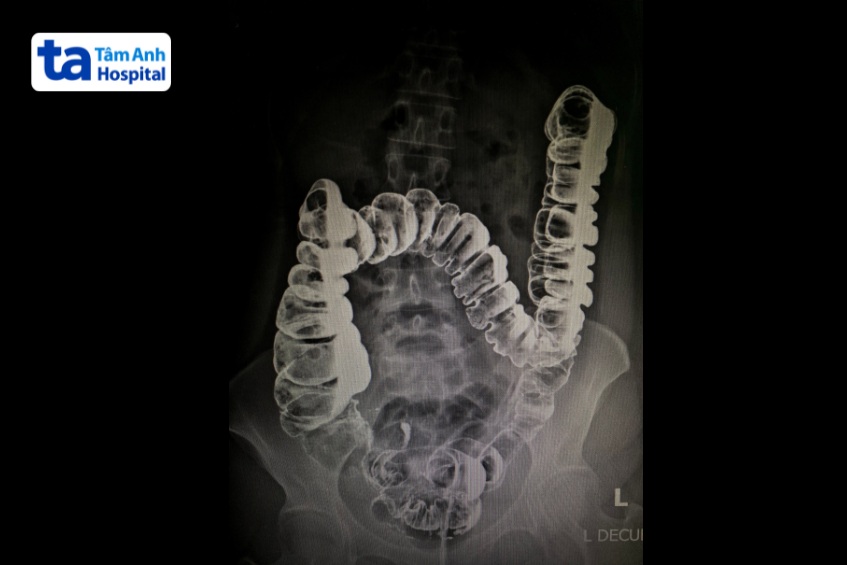

Để điều trị viêm ruột cấp hiệu quả, đầu tiên phải xác định chính xác nguyên nhân gây bệnh và mức độ nghiêm trọng của bệnh lý. Dưới đây là một số phương pháp chẩn đoán thường được bác sĩ chỉ định cho viêm ruột cấp:

Ngoài ra, bác sĩ có thể yêu cầu thực hiện một số phương pháp chẩn đoán hình ảnh như siêu âm ổ bụng, chụp CT hoặc chụp MRI.